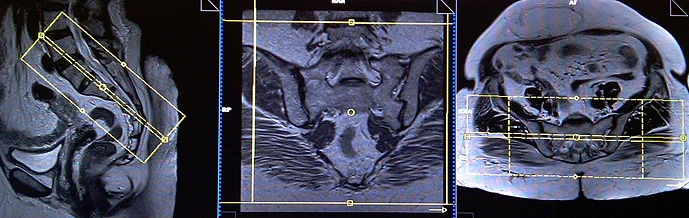

CASE STUDY NO.2

Coronal planning

Axial planning